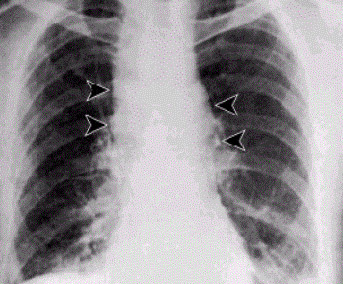

肺炭疽病人X光攝影,可見局部腔室擴大。(維基百科)